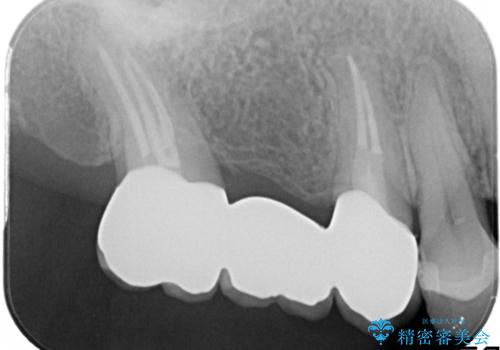

奥歯のオールセラミックブリッジ

- 矯正後に欠損補綴を主訴に来院されました。

オールセラミッククラウンのブリッジ修復にて治療を行っております。

抜歯してから歯周組織が安定するまで期間がかかります。

十分に期間を治癒を待つことで審美性や清掃性の高い被せものを製作できます。